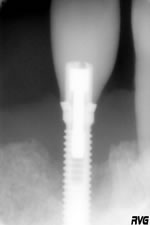

R1-10_03_03

Patient agé de 55 ans porteur dune prothèse amovible (Plaque métallique + 3 dents) au maxillaire, les dents résiduelles (11,12,13) sont légèrement mobiles, CCM sur piliers implantaires au niveau 21,25,27. Prothèse amovible à la mandibule (Plaque métallique + 9 dents). Perte importante de la dimension verticale et problèmes de paro. Le patient se plaint dune douleur diffuse au niveau du pilier implantaire de 21, douleur à la percussion et légère suppuration à la pression digitale (R1 - 10_03_03).